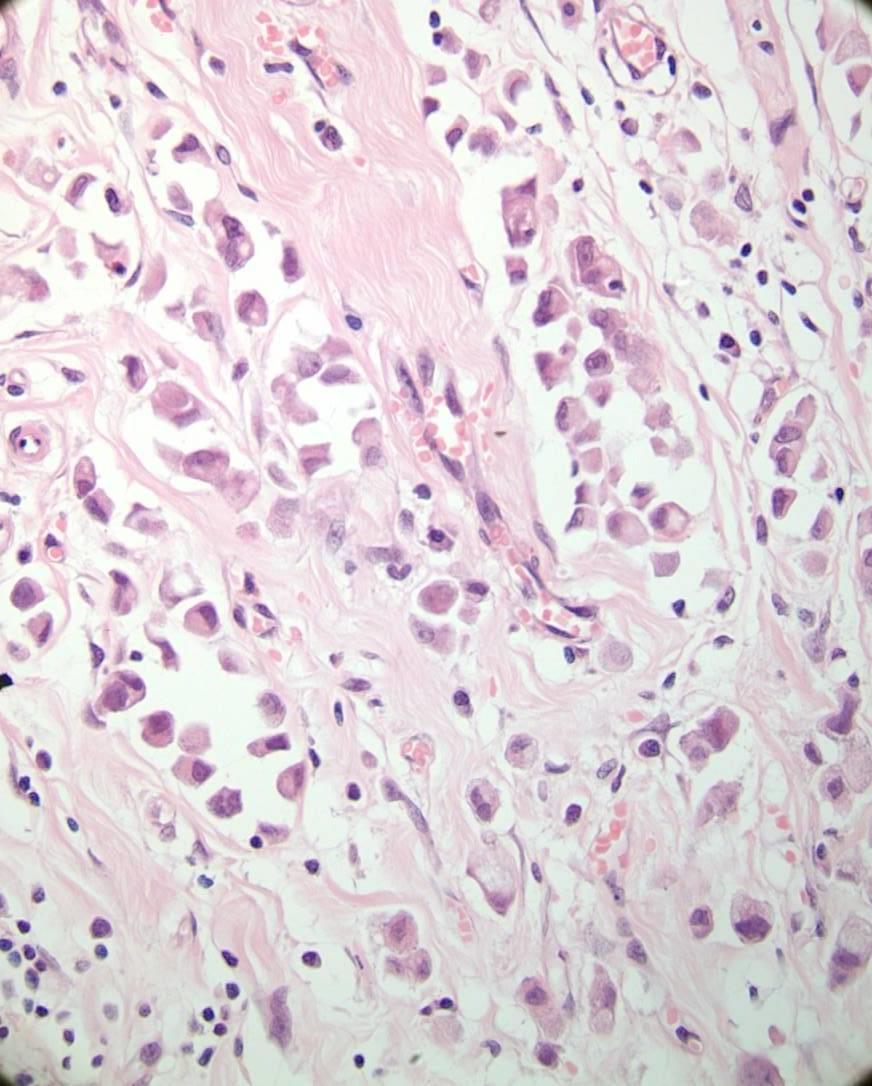

A 63 year old lady presents with nipple erythema and ulceration. A nipple biopsy reveals large round cells with large nuclei, prominent nucleoli and abundant vacuolated cytoplasm within the epidermis. The cells are positive for CK7 and negative for S100. What is the most likely diagnosis?

More frequent in post-menopausal women 1 – 4.3% of all breast cancers Associated invasive carcinoma almost always seen, but rarely (<5%) no carcinoma is found in mastectomy specimens

Defining histologic feature is the presence of malignant glandular epithelial cells within the squamous epithelium of the nipple.

Malignant melanoma Bowen’s disease Clear cell change Toker cell hyperplasia Exclude epidermal infiltration by underlying tumour invading skin

Paget’ s – LMWCK (Cam5.2), CK7, EMA, CEA,

Her2 positive, GCDFP-15, PAS+

Melanoma - S100, melanA, HMB45, SOX-10 positive

Bowen’ s – HMWCK, p63 positive